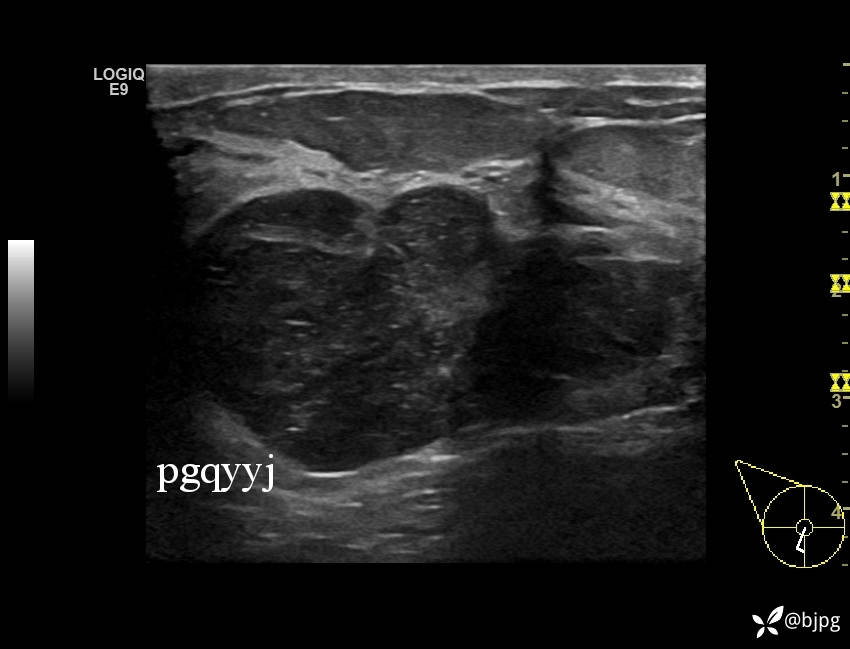

【患者信息】:女性36岁

【主诉】:发现右乳肿物一周

【检查】:超声

【临床诊断】:右乳结节,性质待定

【治疗经过及结果】:穿刺活检,欢迎同道讨论,穿刺病理数日后公布。

乳腺分叶状肿瘤 (7)